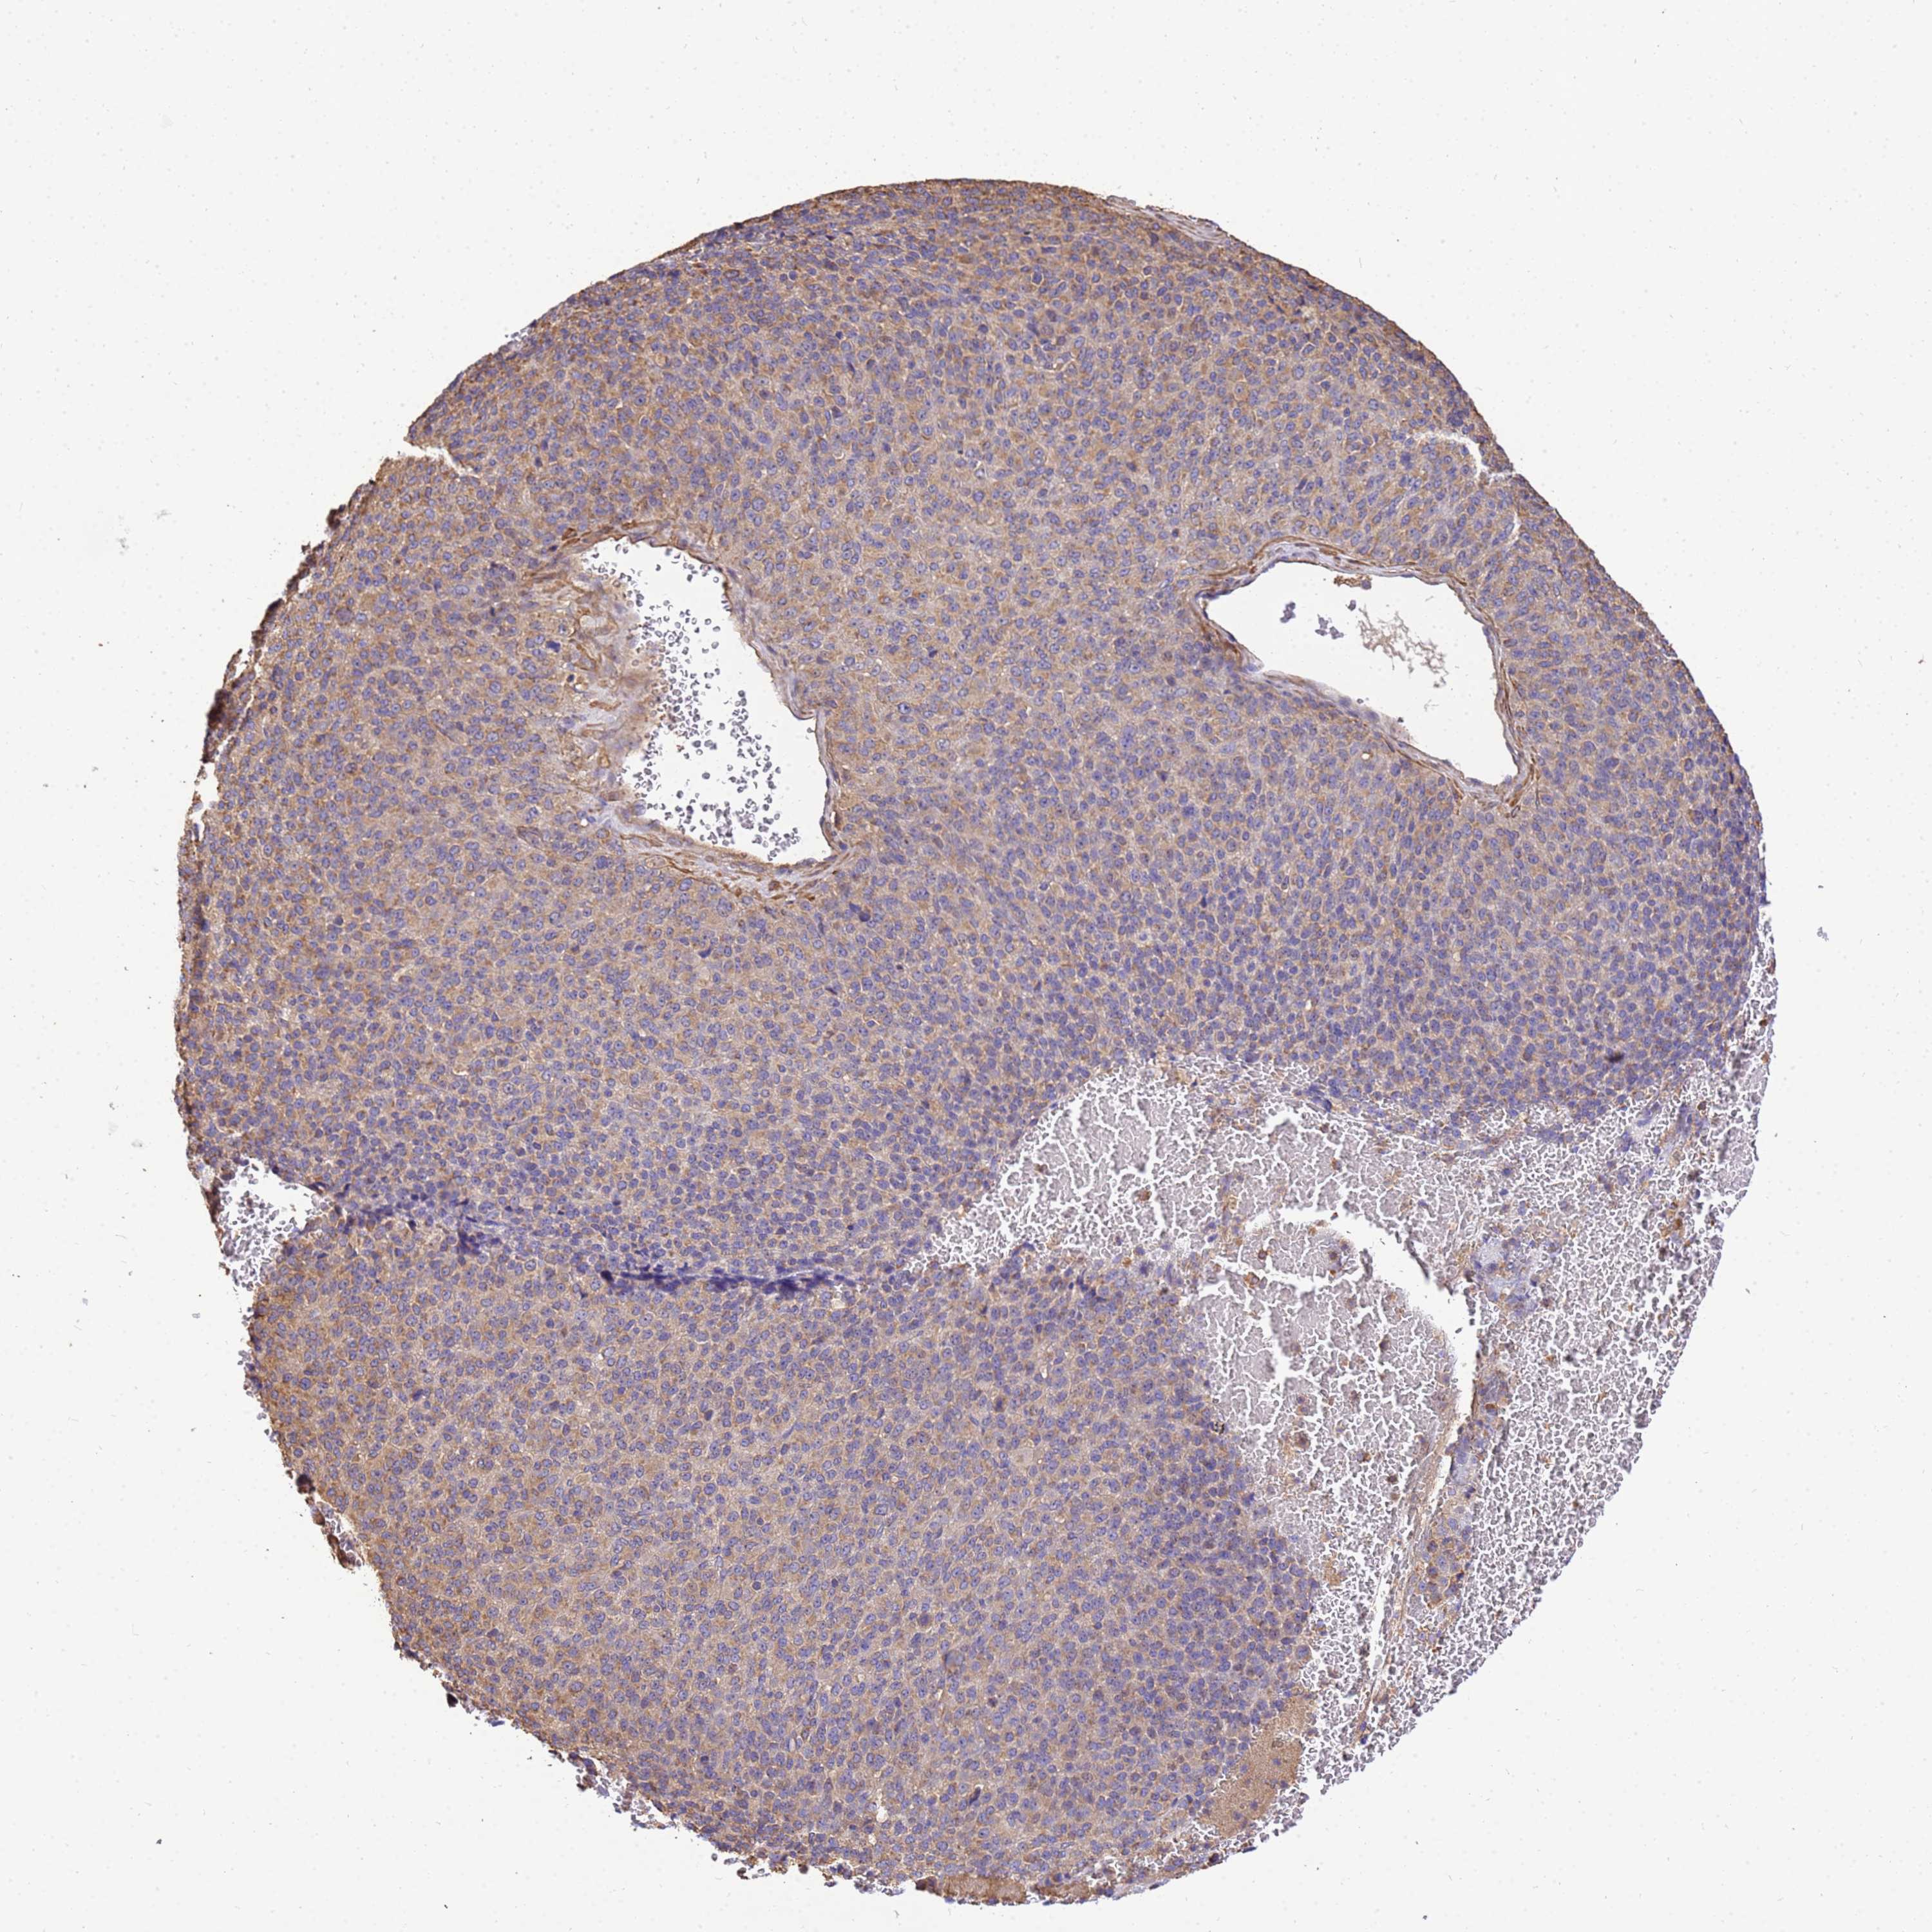

MELANOMA - Protein expressioni

A mouse-over function shows sample information and annotation data. Click on an image to view it in a full screen mode. Samples can be filtered based on level of antibody staining by selecting one or several of the following categories: high, medium, low and not detected. The assay and annotation is described here.

Note that samples used for immunohistochemistry by the Human Protein Atlas do not correspond to samples in the TCGA dataset.

Antibody stainingi

Antibody staining in the annotated cell types in the current human tissue is reported as not detected, low, medium, or high, based on conventional immunohistochemistry profiling in selected tissues. This score is based on the combination of the staining intensity and fraction of stained cells.

Each image is clickable and will lead to virtual microscopy that enables deeper exploration of all samples and also displays staining intensity scores, fraction scores and subcellular localization as well as patient and tissue information for each sample.

Antibody HPA046186

Staining

High

Medium

Low

Not detected

Intensity

Strong

Moderate

Weak

Negative

Quantity

>75%

75%-25%

<25%

None

Location

Nuclear

Cytoplasmic/membranous

Cytoplasmic/membranous,nuclear

Malignant melanoma, NOS

Malignant melanoma, Metastatic site